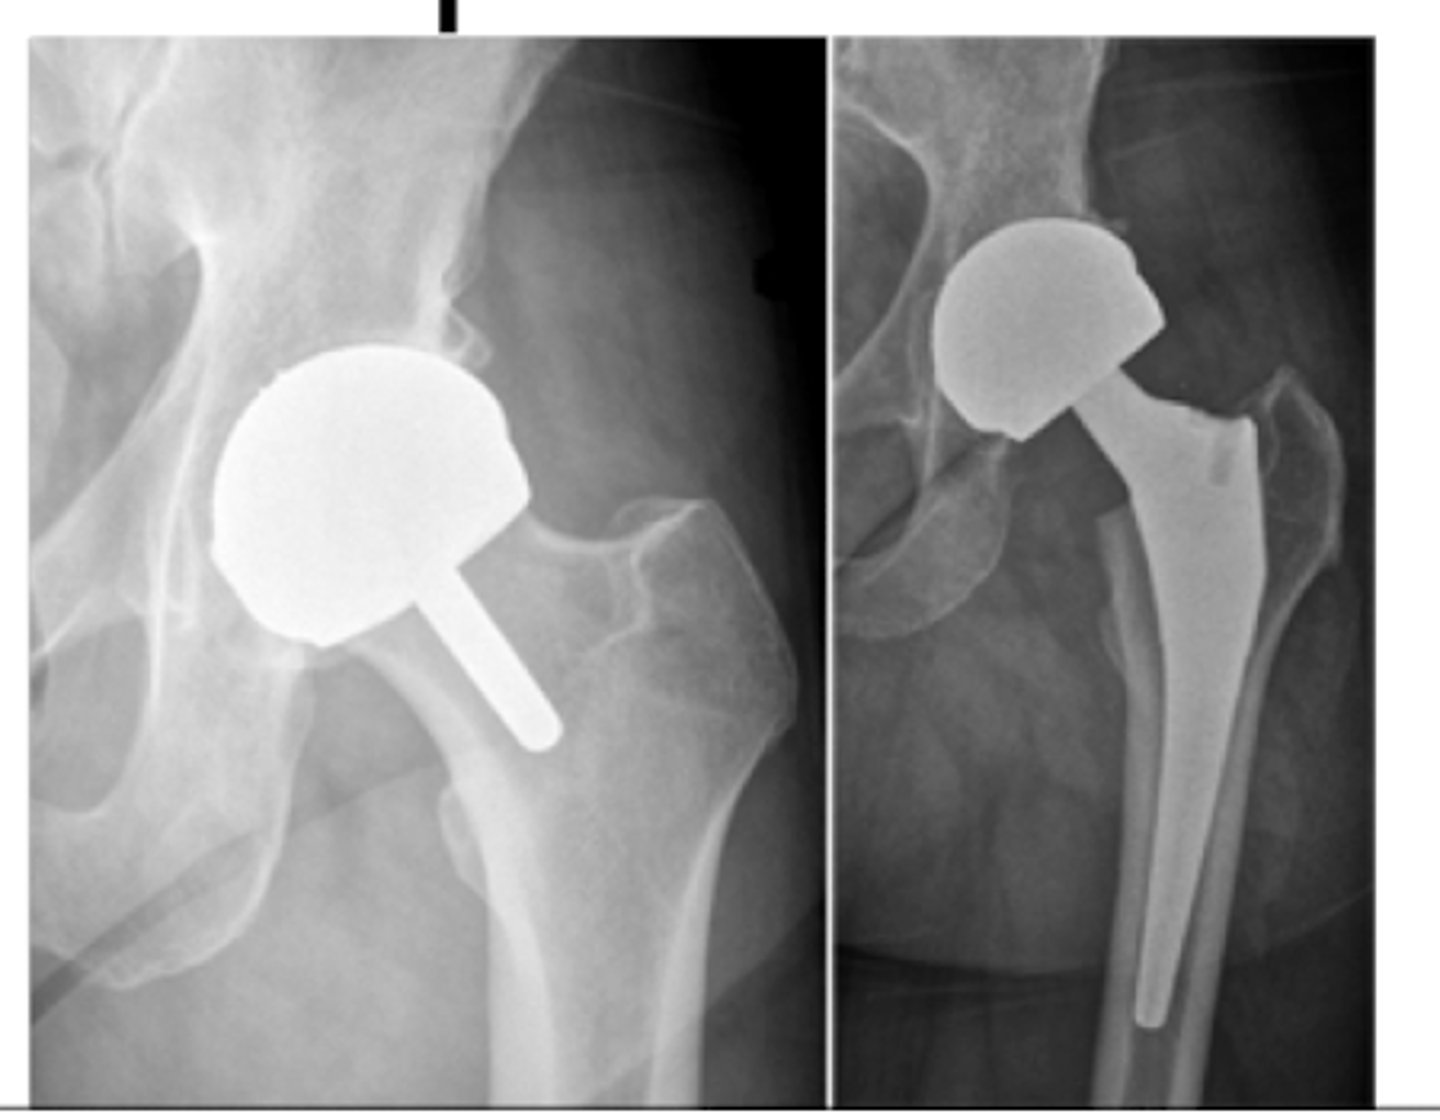

Hip OA

L: bipolar hemiprosthesis

R: unipolar hemiprosthesis

trochanteric osteotomy

used for THA revisions